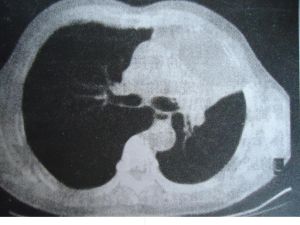

不同部位的肺癌可有以下幾種生長方式:(1)管內型:癌瘤自支氣管黏膜表面向管腔內生長,形成息肉或菜花樣腫塊,逐漸引起支氣管阻塞。

(2)管壁型:癌瘤沿支氣管壁浸潤生長。有時侵犯管壁較淺,使管壁輕度增厚,管腔輕微狹窄。侵及管壁全層,使管壁增厚,管腔明顯狹窄或阻塞。

(3)管外型:癌瘤穿透支氣管壁向腔外生長,主要在肺門區形成腫塊。